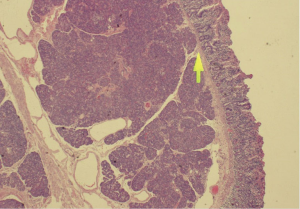

On imaging, plain film abdomen showed dilated small bowel loops and multiple air fluid levels on erect view. Chest X-ray showed no free air under the diaphragm. Computed tomography (CT) of the abdomen and pelvis with IV and oral contrast was done showing prominent dilatation of the jejunal small bowel segments, compatible with obstruction. On the jejunoileal junction and proximal ileal segments there was appearance of intussusception and thickened wall of the ileal segment (6 cm thickness) (Figure 1). Distal ileal and colonic segments were collapsed. There was perihepatic, perisplenic and intrapelvic free fluid. Furthermore, there was a small amount of free air focus in the subhepatic area (Figure 2) with bilateral small pleural effusions. No suspicious lymph nodes were detected.